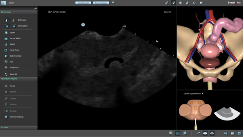

SIMBIONIX U/S MENTOR:

The Simbionix U/S Mentor is a multidisciplinary simulator that will offer hands-on training for diverse ultrasound examinations and interventions, as performed by a rapidly growing number of medical specialties.

The U/S Mentor features a highly realistic simulation within a comprehensive educational environment, supporting independent or instructed hands on training.

The simulation environment combines high level of realism with advanced educational aids, featuring:

- A reliable ultrasound display of anatomy per probe position, incorporating common ultrasound imaging attributes and artefacts.

- Realistic setup with palpable mannequin and true to life anatomies physiology and pathologies.

- Incorporated image enhancement tools, measurement tools, color Doppler, cine-loops recording and clinical findings reporting support training to the full extent of the actual procedure.

- Various educational aids such as anatomy labels, corresponding external visualization, standard views helpers and more are available to accelerate the learning curve and support independent training.